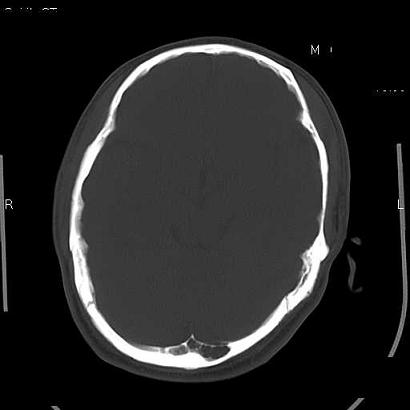

男,39岁,外伤来诊,老师们看看枕骨是什么病

枕内隆突左缘板障区示不规则囊状透亮区,颅骨内外板规整,无膨胀及缺损,周围无软组织肿块,考虑板障血管性病变,1.板障静脉湖,2.枕骨血管瘤(局部无膨胀性改变,无硬化环及钙斑影,故不太支持)。

蛛网膜颗粒压迹不会象这样有清晰的内板显示的!压迹压迹肯定是把内板压到板障里撒!各位老师同意不?